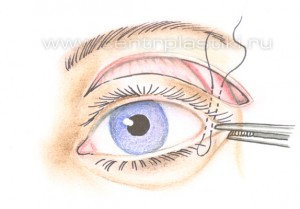

Рис. 9 Через боковую часть разреза выполняется отделение надкостницы от костей в проекции средней зоны лица вниз до крыла носа, обычно для этого используются эндоскопические инструменты. Рис. 11 Мобилизованные ткани прошиваются в верхненаружном углу и фиксируются к надкостнице выше наружного угла глаза. Рис. 12 Выполняется миопексия (фиксация мышцы окружающей глаз) Рис. 13 и кантопексия (фиксация наружного угла глаза), Рис. 14 затем удаляется избыток кожи Рис. 15. Этим достигается правильное положение глазной щели и удается добиться разглаживания мелких морщин. В конце операции кожная рана зашивается косметичным внутрикожным швом.

Рис. 15 С помощью подтяжки средней зоны лица удается получать гармоничное омоложение всей параорбитальной области (области вокруг глаз) и средней зоны лица, особенно у тех, кто имеет выраженные возрастные изменения. Кроме того, прямой вертикальный подъем тканей средней зоны лица (против вектора старения) и редрапировка мышцы окружающей глаз, выполняющиеся в ходе этой операции, приводят к более приятному и естественному внешнему виду лица чем, при подтяжке этой области из височного доступа. Рис. 16.